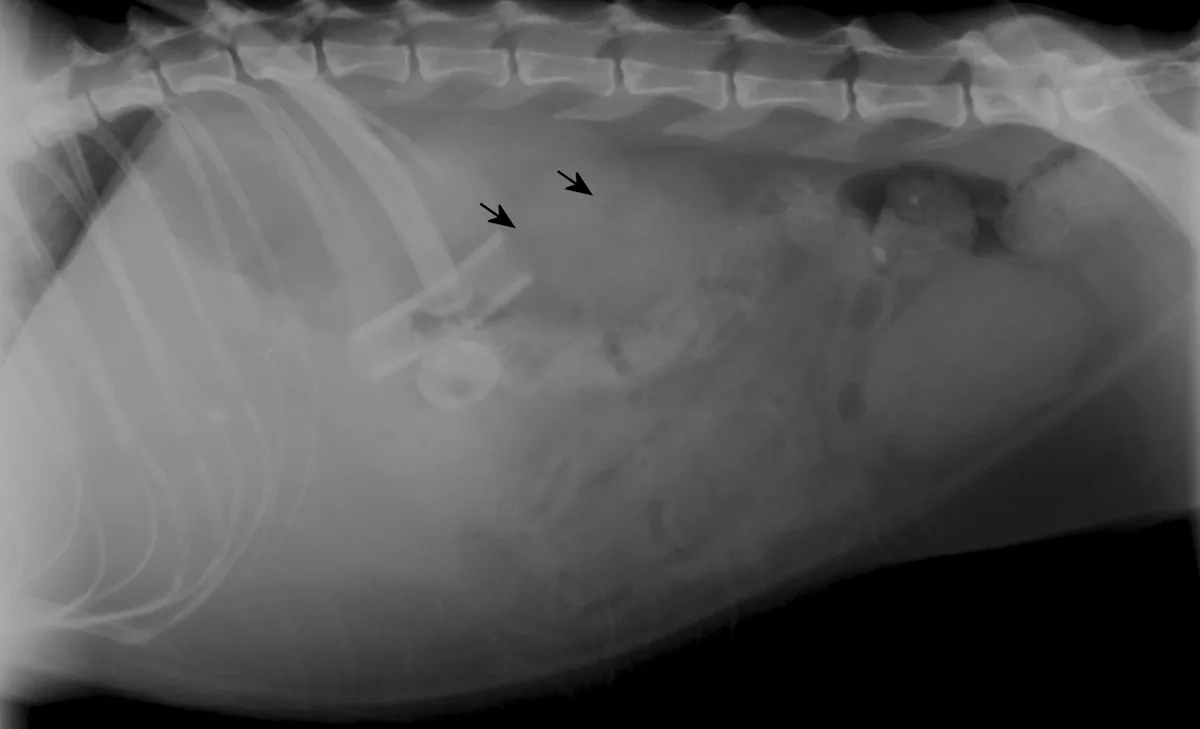

• Figures 4a & 4b. Ventrodorsal and lateral radiographs of percutaneously placed gastrostomy tube showing that the intraabdominal portion of the tube is not contained within the stomach. A number of small, irregularly shaped air bubbles are visible in this region (arrows). There is a mild decrease in midabdominal peritoneal detail that may be caused by the overlying wet hair or peritoneal fluid. (Courtesy of Dr. Eric Ferrell, University of Florida)